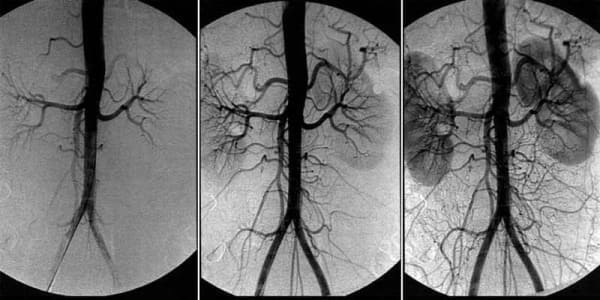

Възстановяването на кръвообращението в мозъка се основава на пречистването на кръвоносните съдове на цялото тяло от натрупаните замърсявания, а именно холестеролни плаки, кръвни съсиреци и калциеви соли.

Възстановяването на кръвообращението и пречистването на кръвоносните съдове е сложен процес. Той засяга всички кръвоносни съдове в тялото и многократно подобрява качеството на живот.